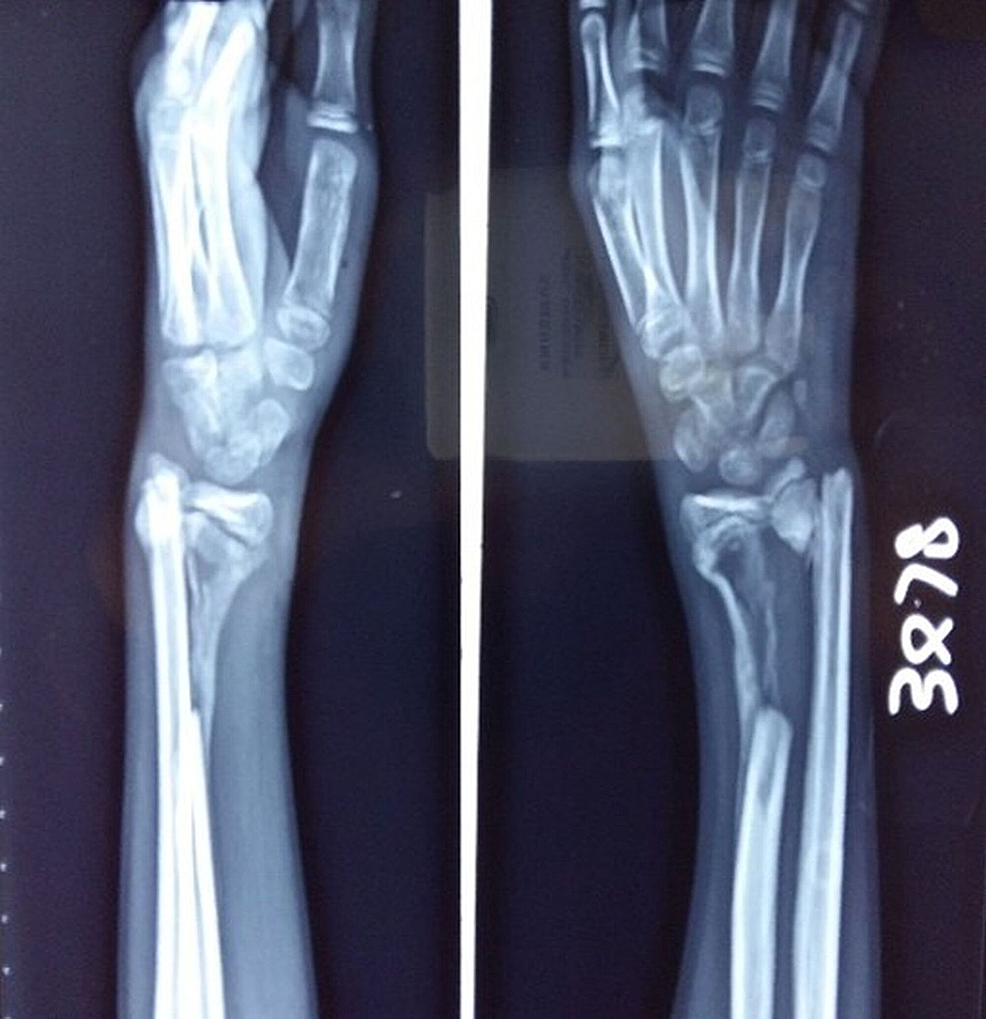

From www.orthoinfo.org

Adult Forearm Fractures OrthoInfo AAOS Spontaneous Bone Fractures Spontaneous insufficiency fractures are caused by normal or physiological stress on weakened bone. 19 rows spontaneous fractures were defined as fractures occurring in long bones in bedridden older people, without any apparent. This is by far the most common reason for a fracture without significant trauma. When there is normal bone but just not enough of it, we call it. Spontaneous Bone Fractures.